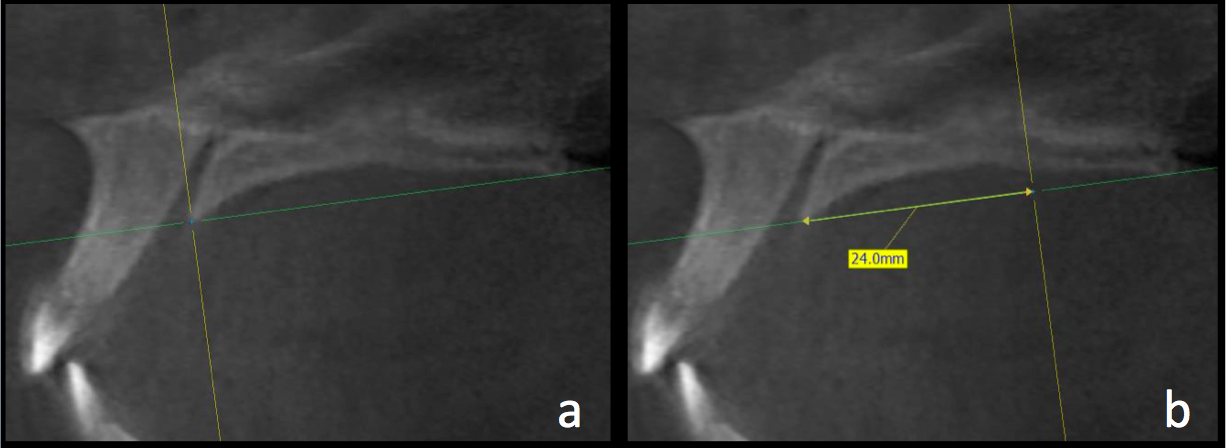

En el corte sagital, las mediciones se realizaron de los 0 a los 24mm, con intervalos de 3 mm entre cada una, con la primera medición en el borde posterior del foramen incisivo (Figura 2). Las mediciones del grosor palatino se realizaron en el corte coronal a los 2, 4, 6 y 8mm, de la sutura media palatina hacia ambos lados (Figura 3).

Intersección de plano axial y coronal a los 0mm (a) y 24mm (b)